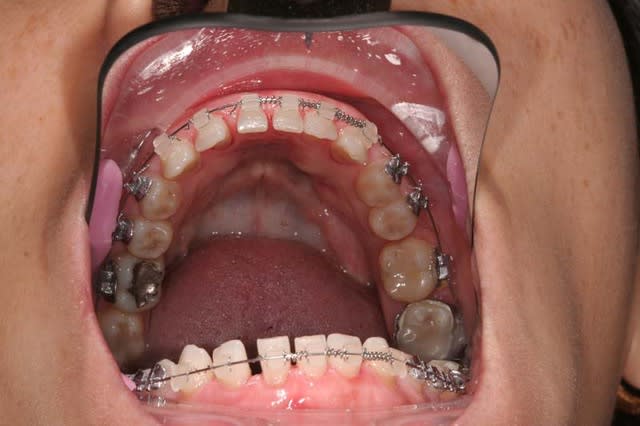

11 a du en passer par l'odf

non la patiente détestait ses diastèmes inf(microdontie relative des inc)

traction en 3 mois

normalement la contention doit être laissée en place 3 mois minimum

cela dit ds ce cas,un ttt odf pr les incisives du bas ayant été entrepris,elle est restée plus longtemps

pr repondre à noa... ce n'est pas moi qui fais l'odf,je me suis contentée de demander,puis de travailler en parrallèle et de concert

l'odf a utilisé un arc 0.014 thermique ,force constante faible

la dent provisoire a été meulée au fur et à mesure de la traction = 3mm

elle a un sourire très gingival et des prothèses déjà en place:la chir de 3 à 3 aurait été plus rapide mais peut être moins esthetique... et je n'ai pas osé....

Tu n'as donc pas nivellé la ligne des collets ?

entre temps il y a de l'odf pr réaligner les incisives du bas(diastèmes se modifient d'après la patiente), à la demande de la patiente et parceque la fracture de 11 au bout de tant d'années me questionne...

la patiente a entamé son traitement odf pr une demande esthetique(marre des diastème)

pr des raisons fonctionnelles aussi,cela ns paraissait une bonne idée

elle a une microdontie relative de ces insicives qui st maintenant redressées, alignées avec des diastèmes equidistants